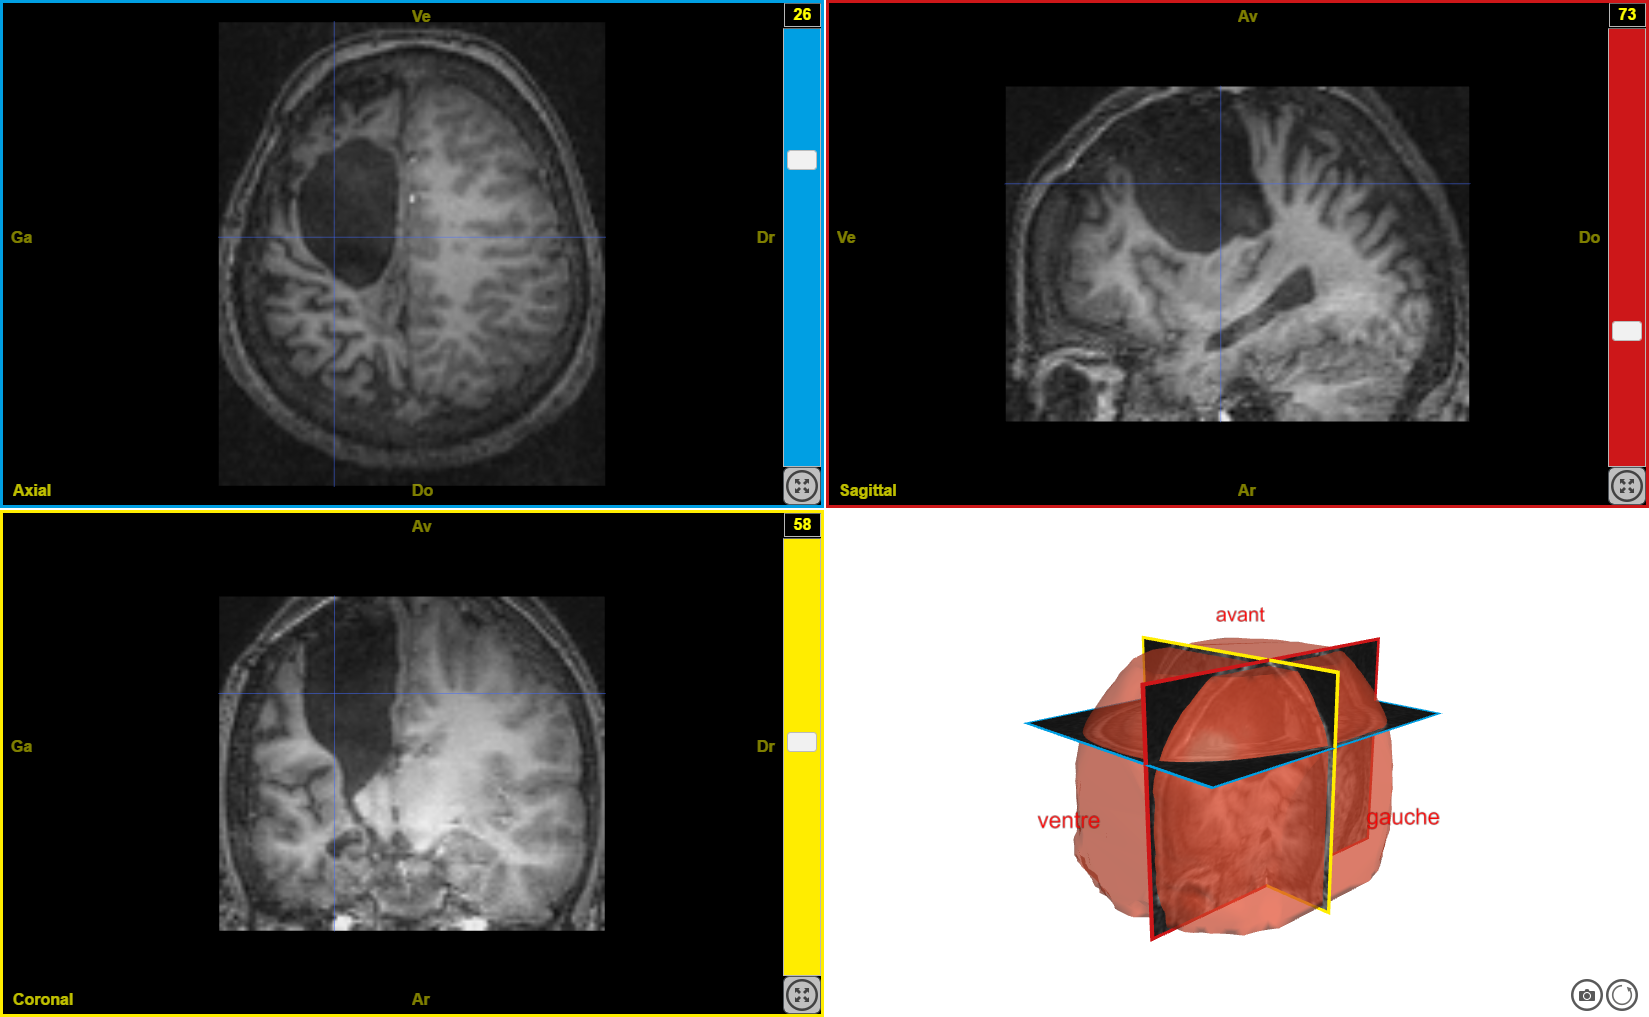

plasti1

Image dans sa taille originale :

423 ko

Ancien logiciel : EduAnatomist et Neuropeda

Informations sur les images AnaPeda

Exemple de lien direct vers EduAnat 2 en ligne